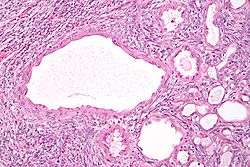

| Micrograph of a cystic nephroma (left of image). Normal kidney is seen on the right. H&E stain. | |

Micrograph of a cystic nephroma. H&E stain.